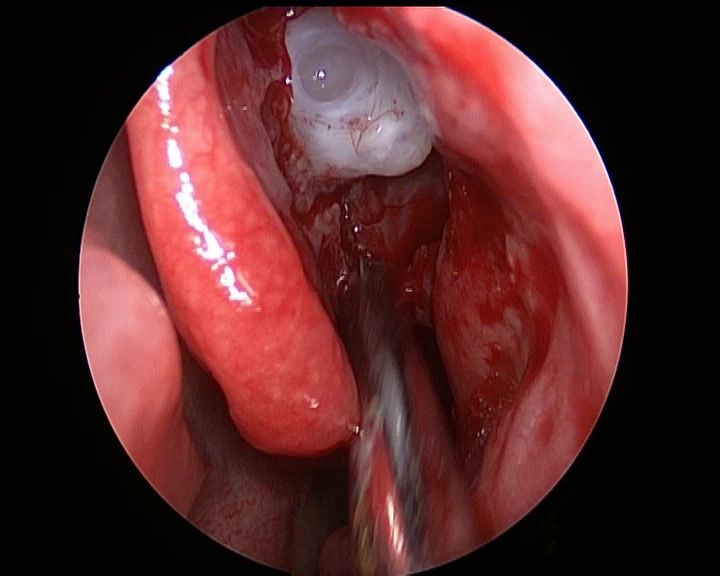

去除钩突、开放筛窦,观察筛房 ↓

↑ 去除筛泡、清理筛窦气房后观察右侧眶纸板